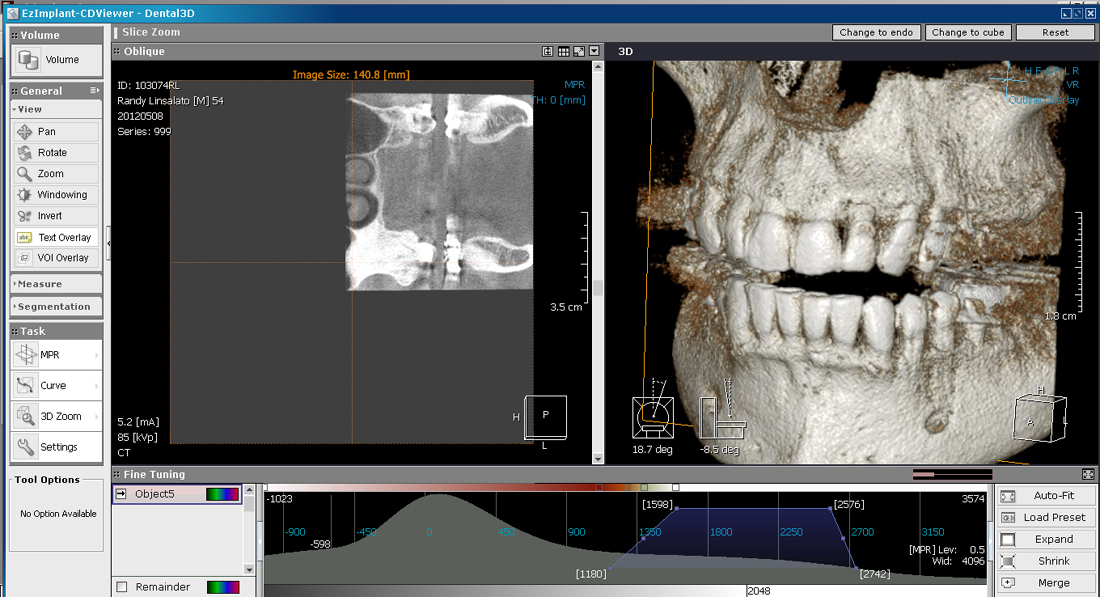

He took the scan below to see the extent of the Osteoma.

As you can see the dense bone mass extends from my lower sinus down around the roots my teeth 14 and 15

Involvement of teeth 13,14, and 15 is obvious.

Bone loss in post treatment CT below

This comparison shows 14 and 15 taken by Fuentes prior to treatment 5-2012 on the left and 9-2016 on the right. Significant bone loss